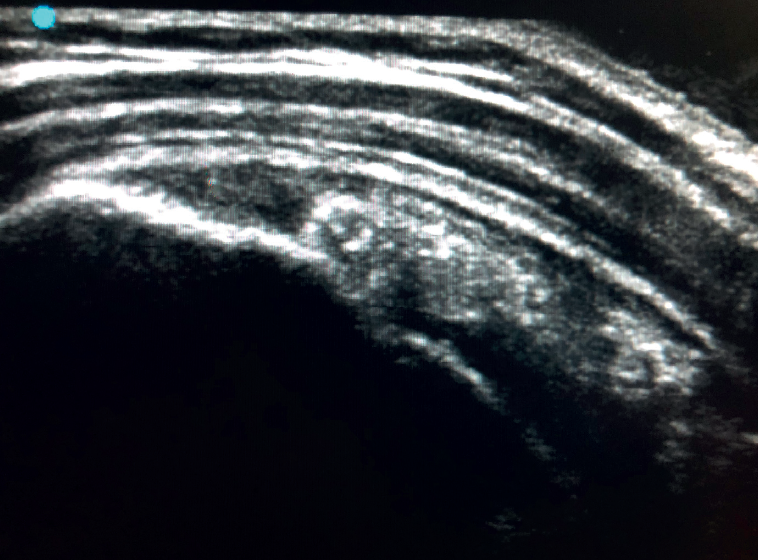

Figure 2. Ultrasound view of the long axis of the tendon of the supraspinatus muscle.

To ensure good ultrasound assessment of the posterosuperior cuff (Figure 2), we instruct the patient to place his or her arm behind the back, with the hand trying to touch the lower vertex of the scapula (Crass position). If the patient is unable to reach or keep this position during the exploration, he or she should be instructed to place the palm of the hand on the ipsilateral anterosuperior iliac crest with the elbow flexed (modification of the Crass position or Middleton position)(25). It is important to explore the tendon to its most anterior margin, as this is a frequent location of symptomatic lesions. For this purpose, in some cases the elbow must be displaced backwards, eliminating the last degrees of internal rotation.